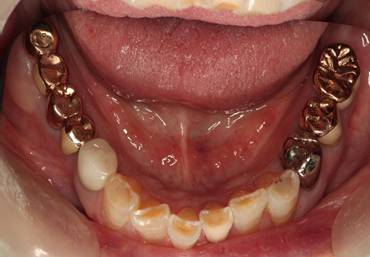

術前。すべての歯が歯周病の末期状態でブリッジ全体がうごいて噛めないとの訴え。右上の犬歯が腫れていました

固定式のブリッジが入っていましたが歯周病で動いています

下顎前歯部には歯石の沈着がみられます

歯周病で抜歯せざるを得ず、インプラントを希望されたケース(使用インプラントはスプライン)